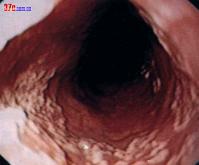

1.內鏡檢查 常見食管黏膜充血、水腫、潰瘍、假膜及局部脆性增加。

2.內鏡活檢病理如在黏膜下層見到較多的細菌即可確立診斷。

3.通過纖維胃鏡行膿腫引流 可在胃鏡下通過注射針抽吸膿腫部位的膿液以達到部分引流的目的。